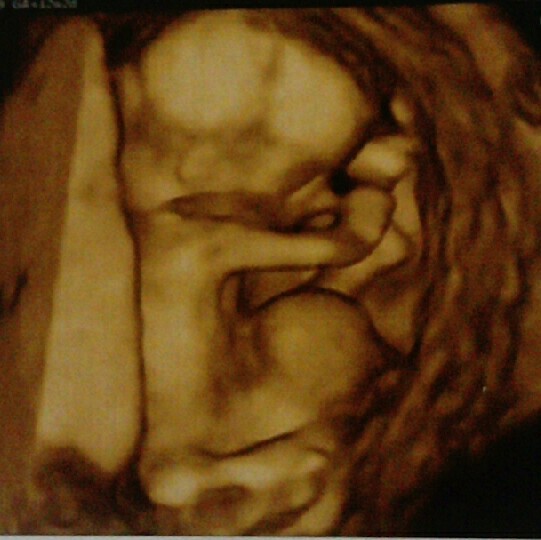

Zobacz załącznik 1173862